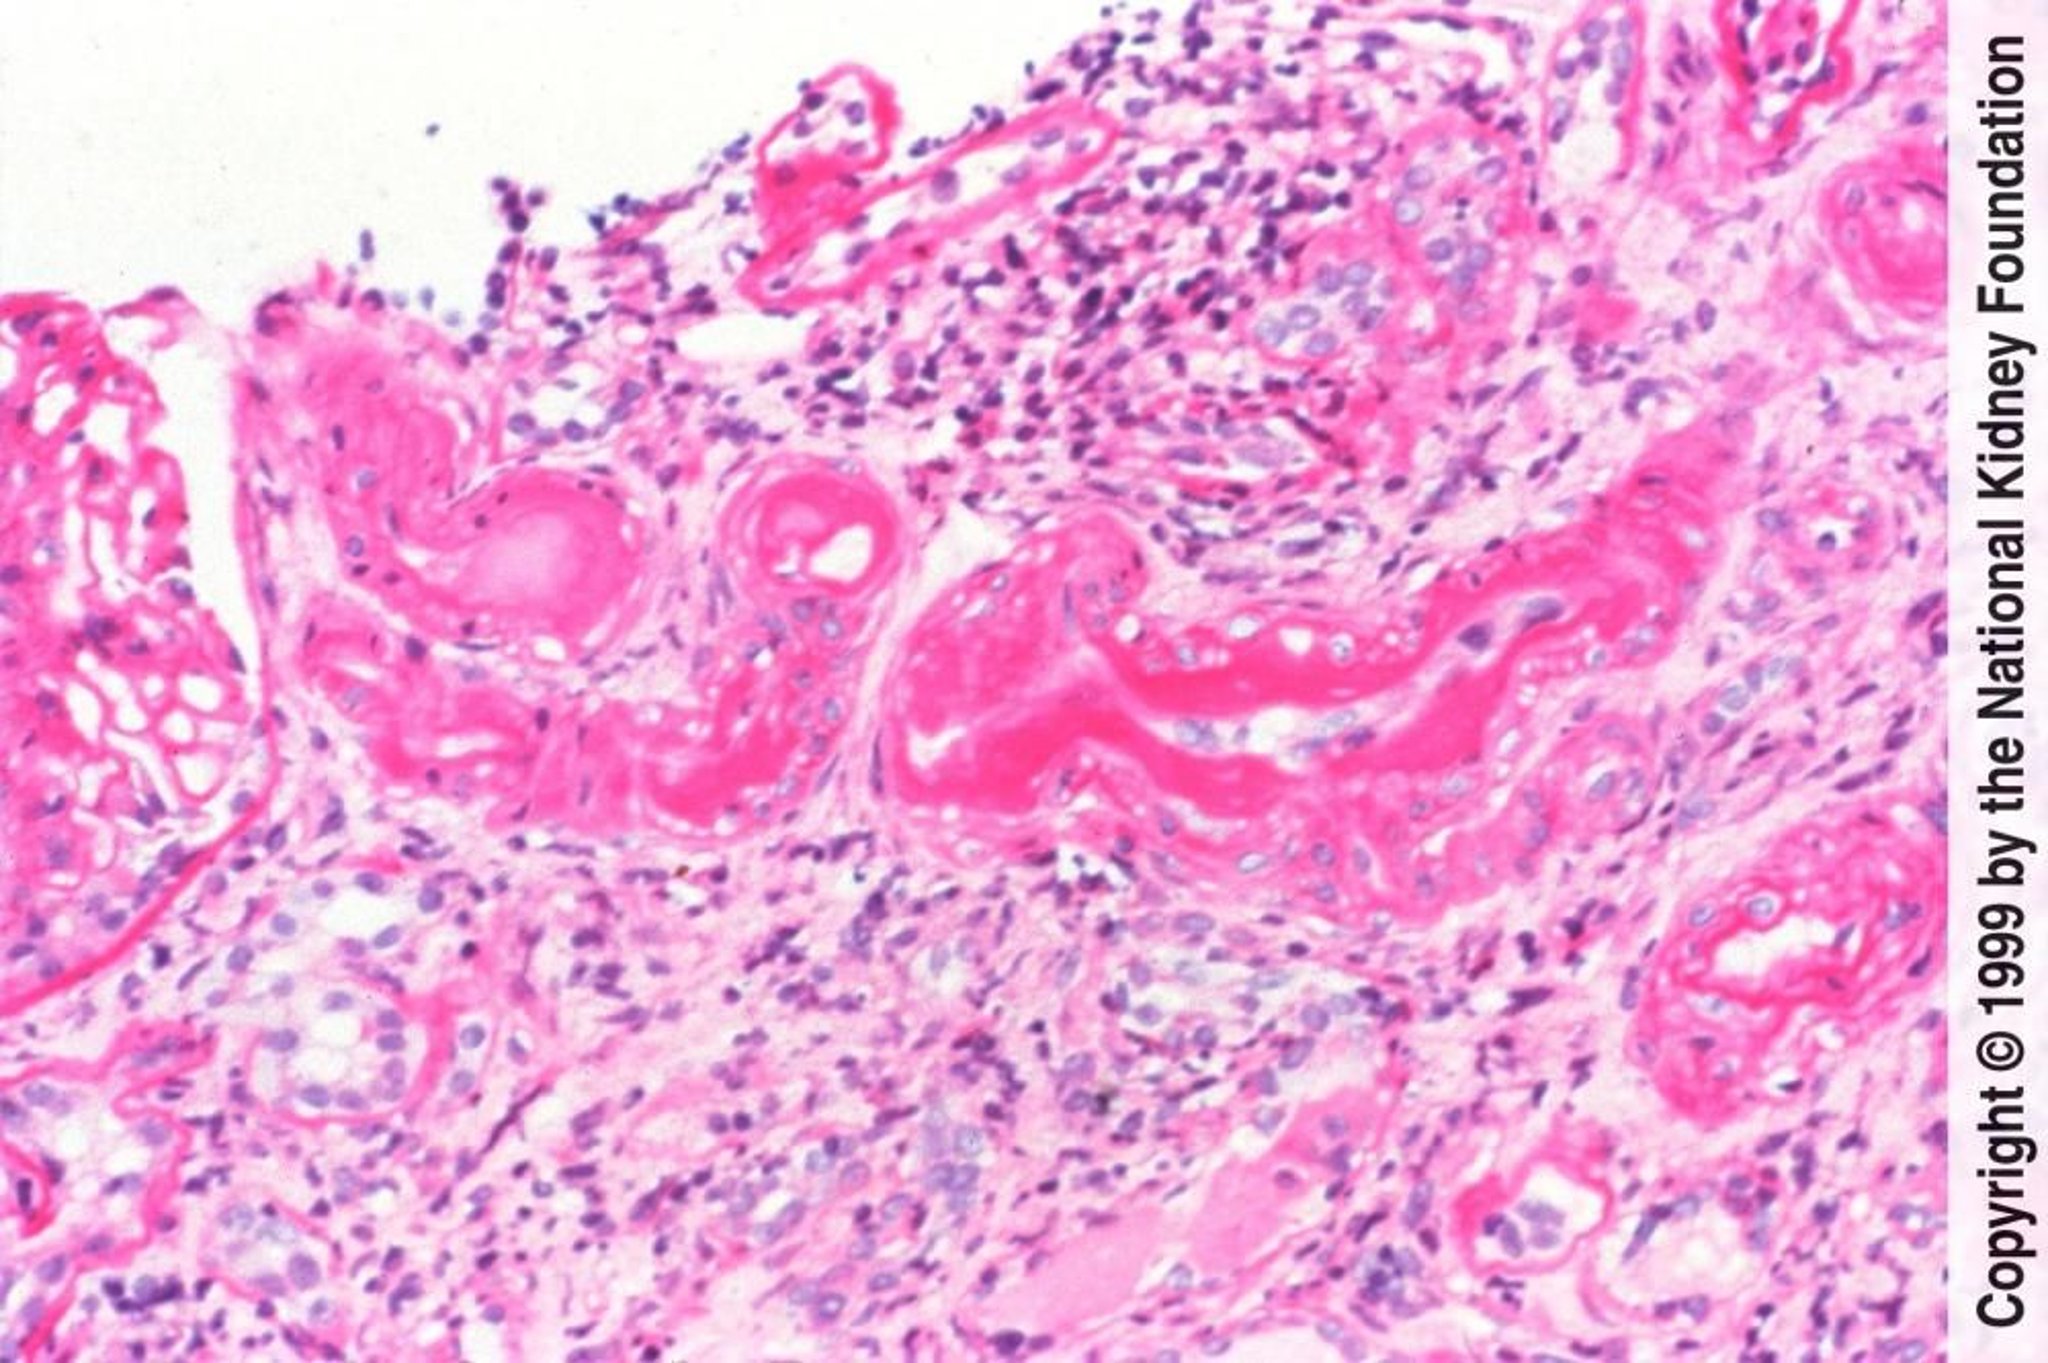

Nefroangiosclerosi arteriolare ipertensiva benigna

La nefrosclerosi arteriolare ipertensiva benigna è caratterizzata istologicamente dall'ialinosi arteriolare causata dall'insudazione di proteine plasmatiche e dall'ispessimento della media causato dall'ipertrofia e dall'iperplasia delle cellule muscolari lisce vascolari (acido periodico di Schiff, × 200).

Imagine fornita da Agnes Fogo, MD, and the American Journal of Kidney Diseases' Atlas of Renal Pathology (vedi www.ajkd.org).